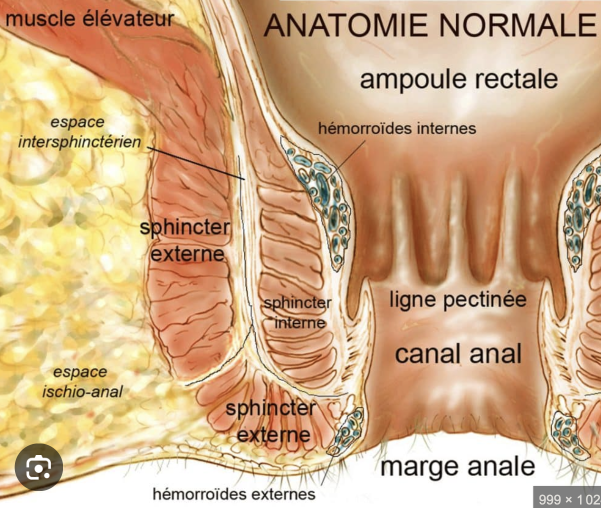

Anatomie et Classification

- Muscle releveur de l’anus comprenant le pubo-rectal et l’ilio-coccygien

- Sphincter Interne

- Sphincter Externe